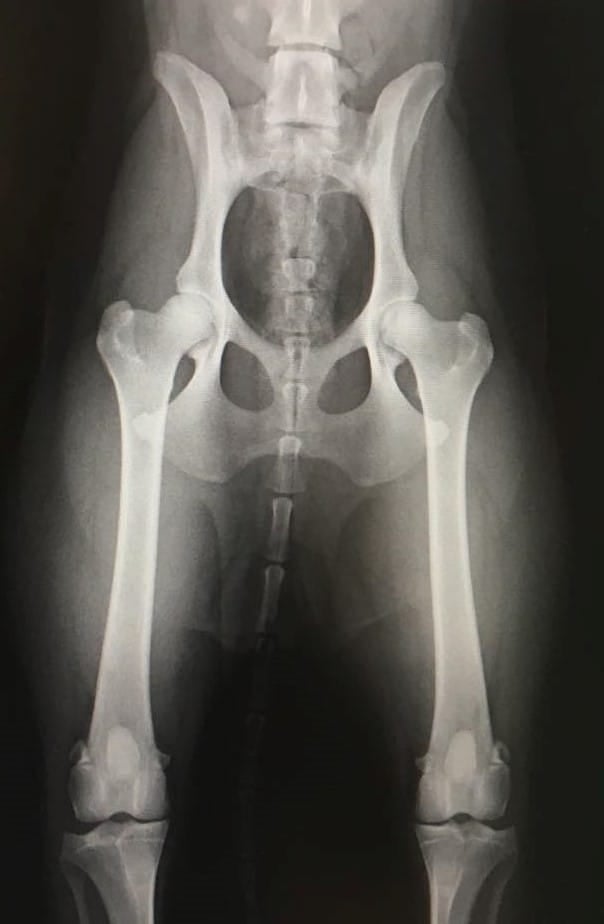

HD-Hofteledsdysplasi

HD er forandringer i hofteledet, hvor lårbenshovedet ikke passer optimalt ind i hofteskålen. Det vil med tiden medføre fejlbelastning af leddet. HD har en lav til middelhøj arvbarhed og nedarves polygenetisk.

Dvs. at flere gener har betydning for om hunden er disponeret for at udvikle lidelsen, men sygdommen kan også påvirkes negativt af miljøet, herunder forkert fodring, overvægt.

Ud fra bedømmelse af et røntgenbillede af hofterne, vil hunden få tildelt en status fra A til E. Hunde med HD status A og B, betragtes som værende fri for HD.

Hunde med C status betragtes som mild, dernæst HD status D som værende moderat, og til sidst HD status E, som værende en svær graf af HD.

En HD-fotografering er derfor en klinisk vurdering af hoften.

Husk, at en hund skal gå på sine ben, og ikke sine røntgenbilleder!

Billedet til venstre er modtaget af en hvalpekøber fra Cooper´s første kuld.

Jeg er meget taknemlig for ejeren ønskede at undersøge sin hund.

Hunden fik bedømmelse HD: A